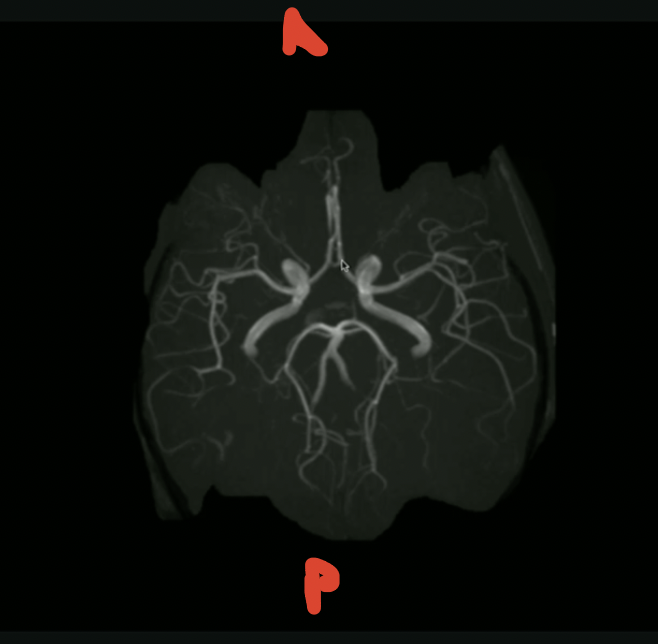

<p>What is the orientation + what are these vessels?</p>

What is the orientation + what are these vessels?

knowt flashcard image